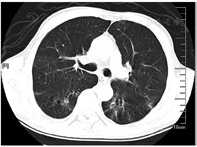

住院期间患者治疗极不配合、烦躁、拒绝交流,症状逐渐加重,入院后第15天心理科会诊加用奥氮平2.5 g夜间鼻饲、草酸艾司西酞普兰片10 mg 1次/d鼻饲,服药2 d后症状好转,同时P/F上升至253 mmHg,气道分泌物减少,逐步间断撤离呼吸机。入院后第17天复查CT示两肺多发炎症,较前吸收,右肺下叶炎性小结节,双侧胸膜增厚(图3)。患者入院后第19天,呼吸机撤离24 h后动脉血气分析:pH 7.48,PaO2 199 mmHg,PaCO2 36.1 mmHg,P/F 485 mmHg,予更换金属气管导管,后患者经口进流质呛咳,喉镜检查咽喉部未见明显异常。入院后第24天拔除金属气管导管。患者病情平稳,办理出院回当地医院治疗。出院诊断:戊二醛中毒、吸入性肺炎、肺部感染。出院后当地医院继续予抗感染、化痰等对症支持治疗。发病1个月后随访,患者未诉不适,已停用奥氮平和草酸艾司西酞普兰片;8月5日复查胸部CT示两肺渗出基本吸收(图4),3个月后随访未出现吞咽困难、呼吸困难等症状,未留有后遗症。

两肺渗出进一步吸收,右肺下叶炎性小结节可能

右肺下叶小结节